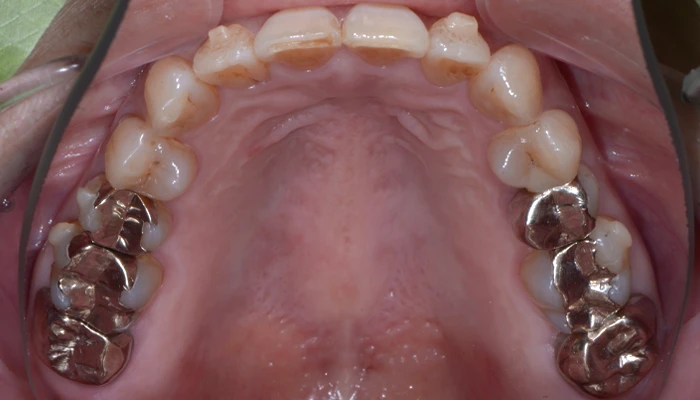

治療例12. 上下の部分矯正

治療前

経過

治療後

主訴 | 八重歯と咬み合わせを治したい |

---|---|

治療期間 | 9ヶ月 |

治療費 | 40万+tax (別途調整料) |

治療内容 | 上下顎ラビアル矯正(表側矯正) |

治療のリスク | 後戻り |